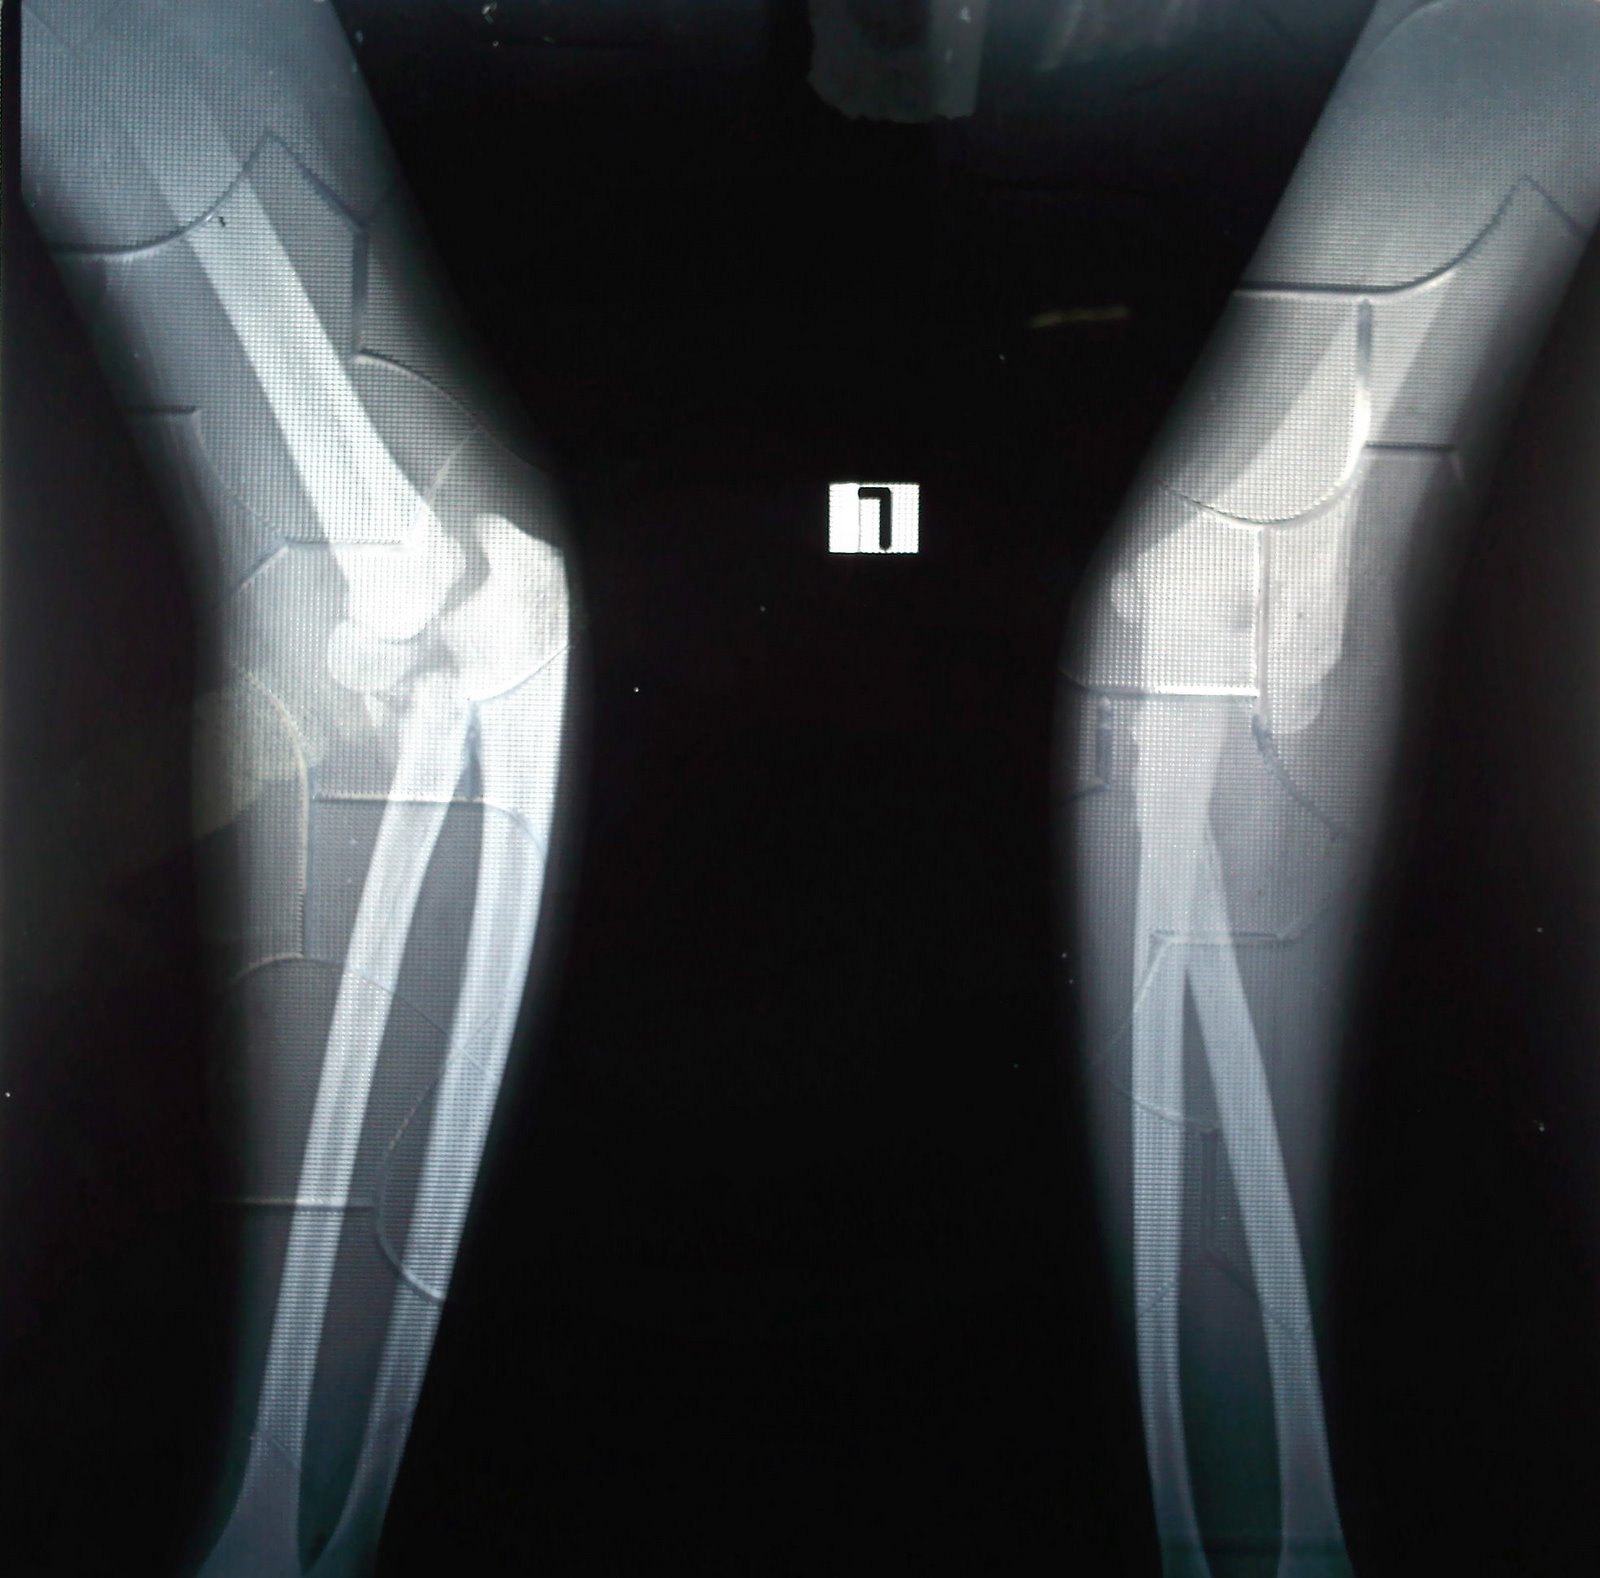

Cubitus varus (gunstock deformity) MedicoLearning

Gunstock deformity MEDizzy Gun Stock Deformity Hip  Stulberg and associates back in. The aim of the study. It was first described by dr. Web a decreased head/neck offset has been recognized on ap pelvic views and labeled as pistol grip deformity. Web pistol grip deformity describes the abnormal shape of the hip joint. Web  dr tushar agarwalcabitus varus the gun stock present by wiroc associated with. Web. Gun Stock Deformity Hip.

Cubitus Varus / Gun Stock Deformity PreTreatment and Post Treatment Gun Stock Deformity Hip  Web early hip joint degeneration is a common clinical presentation and preexisting abnormal joint morphology is a risk factor for its. Web a decreased head/neck offset has been recognized on ap pelvic views and labeled as pistol grip deformity. The aim of the study. Web  dr tushar agarwalcabitus varus the gun stock present by wiroc associated with. It was first. Gun Stock Deformity Hip.

Cubitus varus and cubitus valgus deformity, Gunstock deformity of elbow Gun Stock Deformity Hip  Web a decreased head/neck offset has been recognized on ap pelvic views and labeled as pistol grip deformity. It was first described by dr. Web early hip joint degeneration is a common clinical presentation and preexisting abnormal joint morphology is a risk factor for its. The aim of the study. Web  dr tushar agarwalcabitus varus the gun stock present by. Gun Stock Deformity Hip.